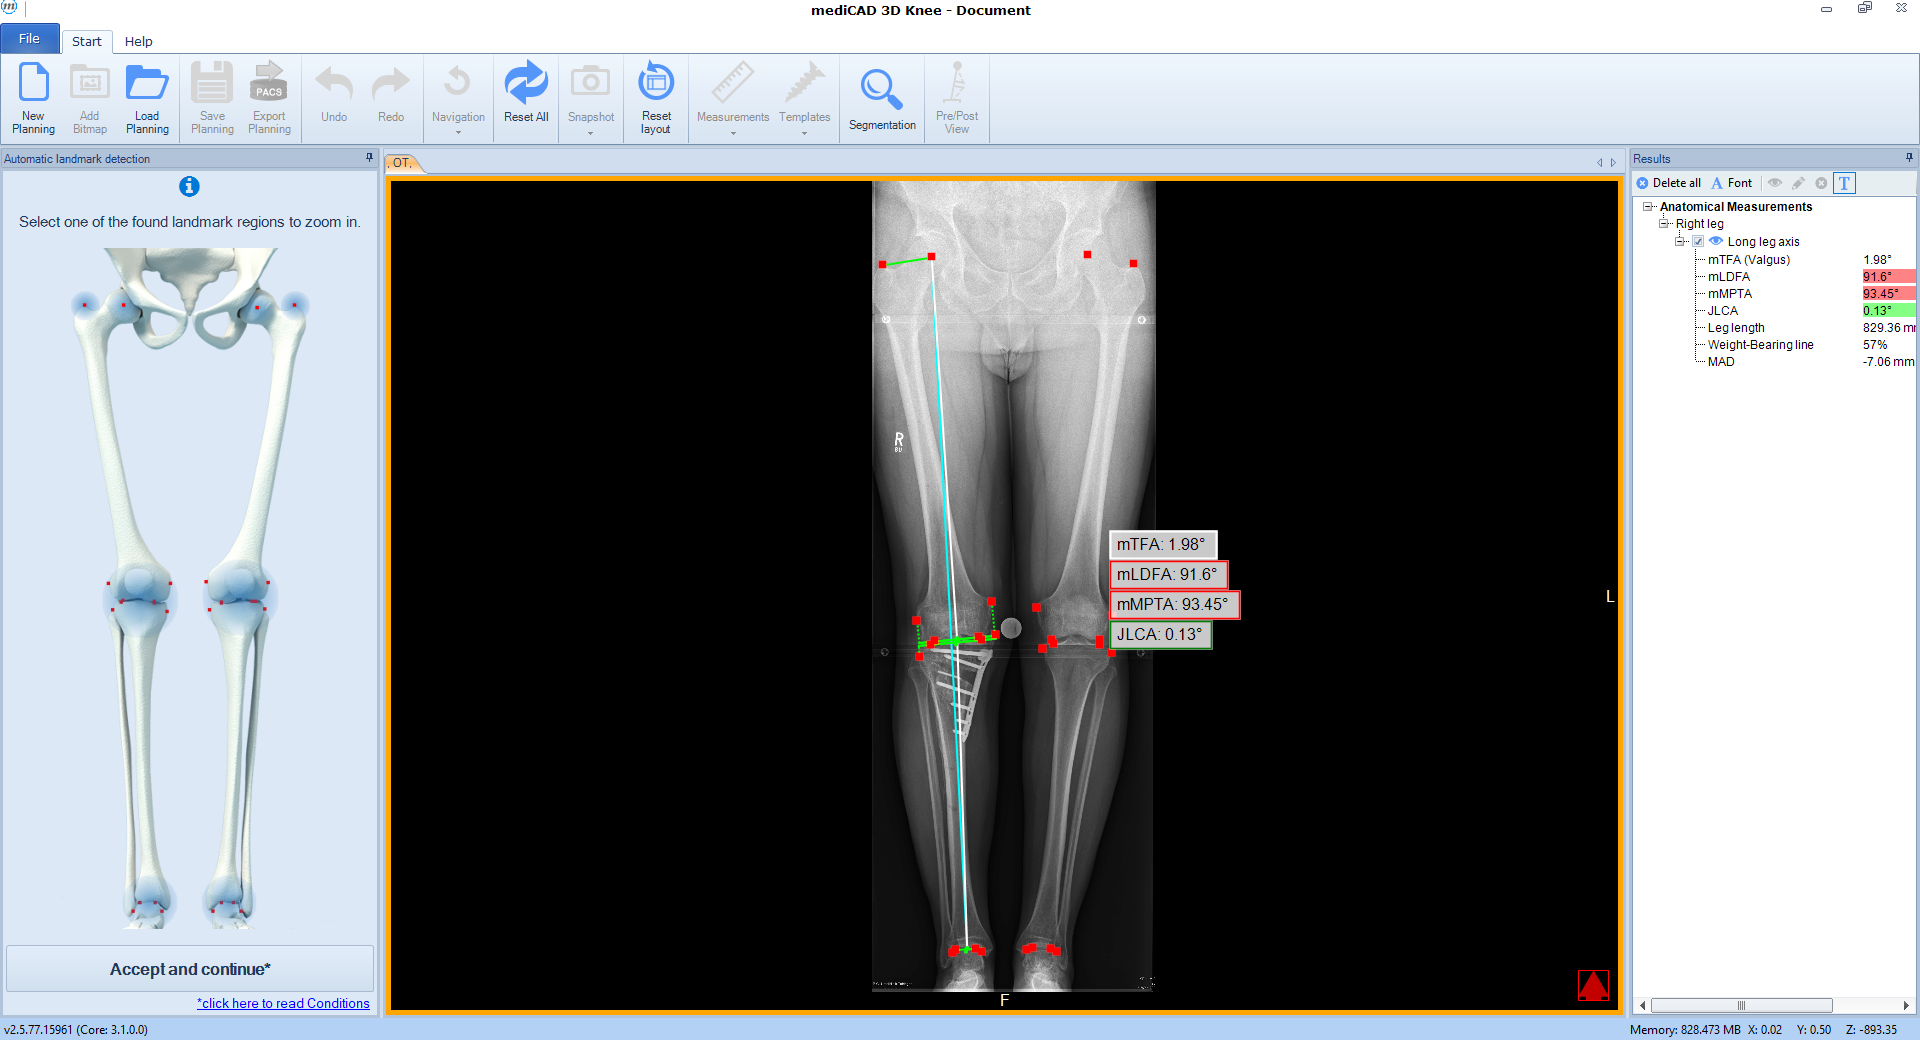

The software automatically detects all necessary landmarks (Fig 1). Based on their position (which can be adjusted manually) the software calculates all essential values (axis, joint lines, and angles) and delivers a detailed report. A traffic light system illustrates normal, intermediate, or pathological values.

Case 1

(Case provided by Stefan Schröter)

A 33-year-old woman complained of pain in the lateral compartment after a normal working day. Sports activities were no longer possible. Free range of motion (ROM: 0/0/150°), ligaments in sagittal, and coronal planes were stable. There was no effusion. The patient had valgus deformity which was corrected with a distal femoral osteotomy.